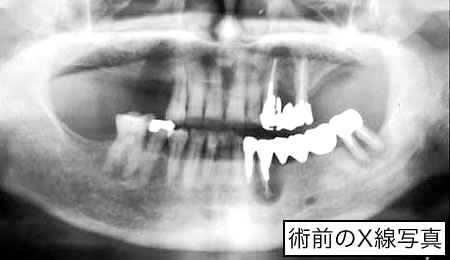

最近のインプラント治療は、以前のように、噛めることを優先とした治療だけでなく、見た目(審美性)まで考慮した治療へと移行してきています。また、以前までは、骨がない部分にはインプラント治療はあきらめざるを得なかったところに、骨を再生させ、骨量を増大させることによりインプラントを植立することが可能になってきています。しかし、このような治療には術者の高度な技術が要求されるのも確かです。

また、インプラント治療を受けられる患者さんでは、その他の歯牙や歯周組織においても問題を抱えている場合が多く、一口腔単位での治療が必要になる場合がほとんどであるといえます。噛み合わせや歯の根っこの治療(根間治療)、歯周治療、虫歯の治療をおろそかにしてインプラント治療の成功は望めないといっても過言ではないでしょう。 |